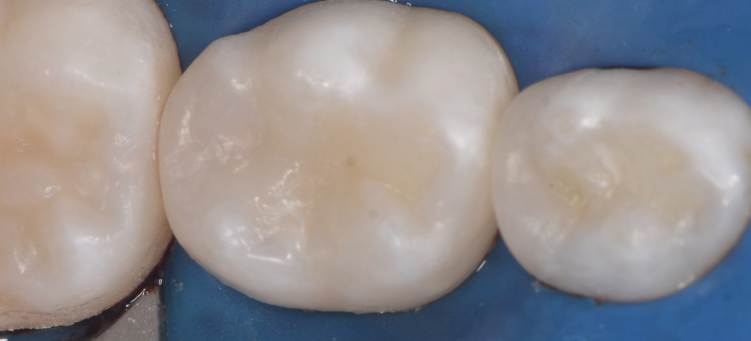

Лечение кариеса